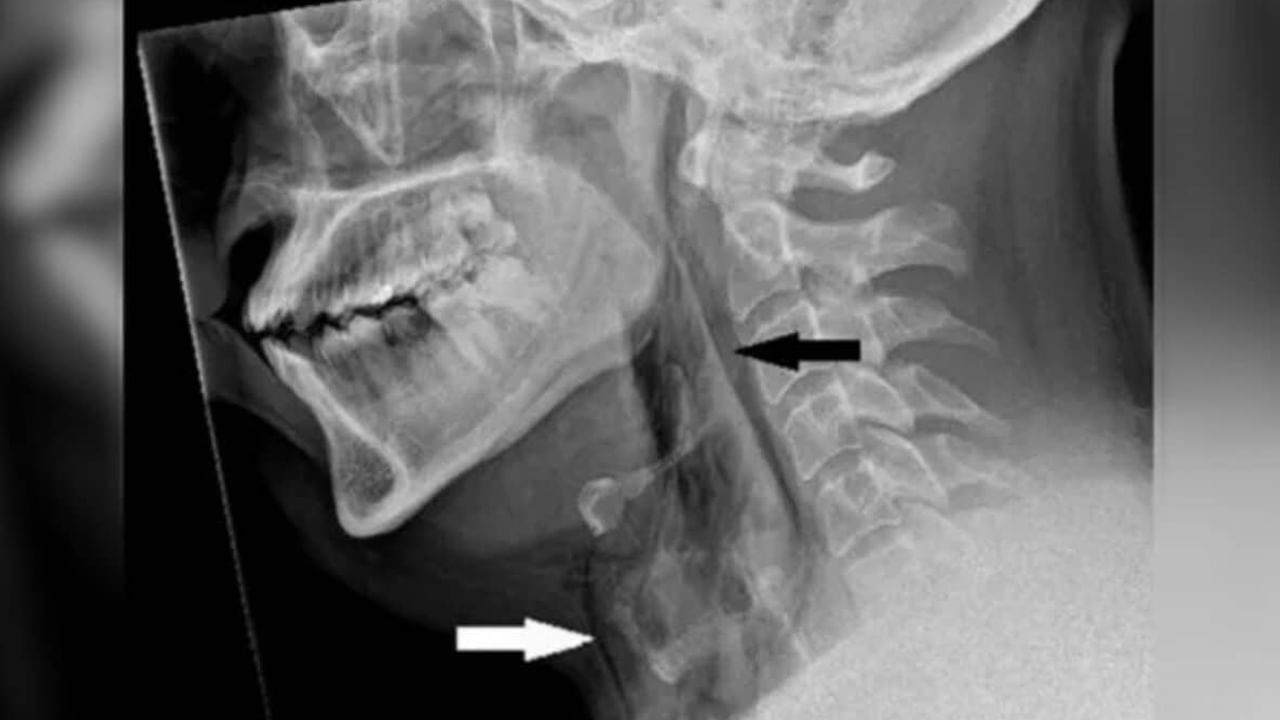

తీవ్రమైన మెడనొప్పి, మెడ అటూ, ఇటూ కదపలేకపోతున్నాడు. మెడ చుట్టూ వాపు కూడా ఉంది. దీంతో వెంటనే డాక్టర్లను సంప్రదించాడు. ఈ ఇబ్బందులు ఉన్నప్పటికీ అతను శ్వాస తీసుకోవడం, మింగడం, మాట్లాడటంలో ఎలాంటి ఇబ్బంది లేదు. దీంతో ఎక్స్ రే, సీటీ స్కాన్ తీశారు డాక్టర్లు. రిపోర్ట్ చూడగా...

ఆ తర్వాత అతనికి మెడ నొప్పి, వాపు వచ్చాయి. మెడ కదలడం కష్టమైపోయింది. దీంతో అతను ఆస్పత్రికి వెళ్లగా.. టెస్టులు చేసిన డాక్టర్లు గొంతులో చిన్న చిల్లు ఉండటాన్ని గుర్తించారు. తుమ్మినప్పుడు… ముక్కు నొక్కి, నోరు మూసుకుని ఆపడం వల్ల.. గొంతులో గాలి చాలా బలంగా నిలిచిపోయింది. ఇది గొంతు లోపల ఒత్తిడి పెంచి పగిలిపోయేలా చేసింది. ఆ వ్యక్తికి శస్త్రచికిత్స అవసరం లేకుండా, కొన్ని రోజులు ఆసుపత్రిలో ఉంచి గమనించారు. రెండు వారాలు శ్రమకు దూరంగా ఉండాలని చెప్పారు. ఐదు వారాల తర్వాత అతని గొంతు పూర్తిగా మామూలు అయ్యింది.